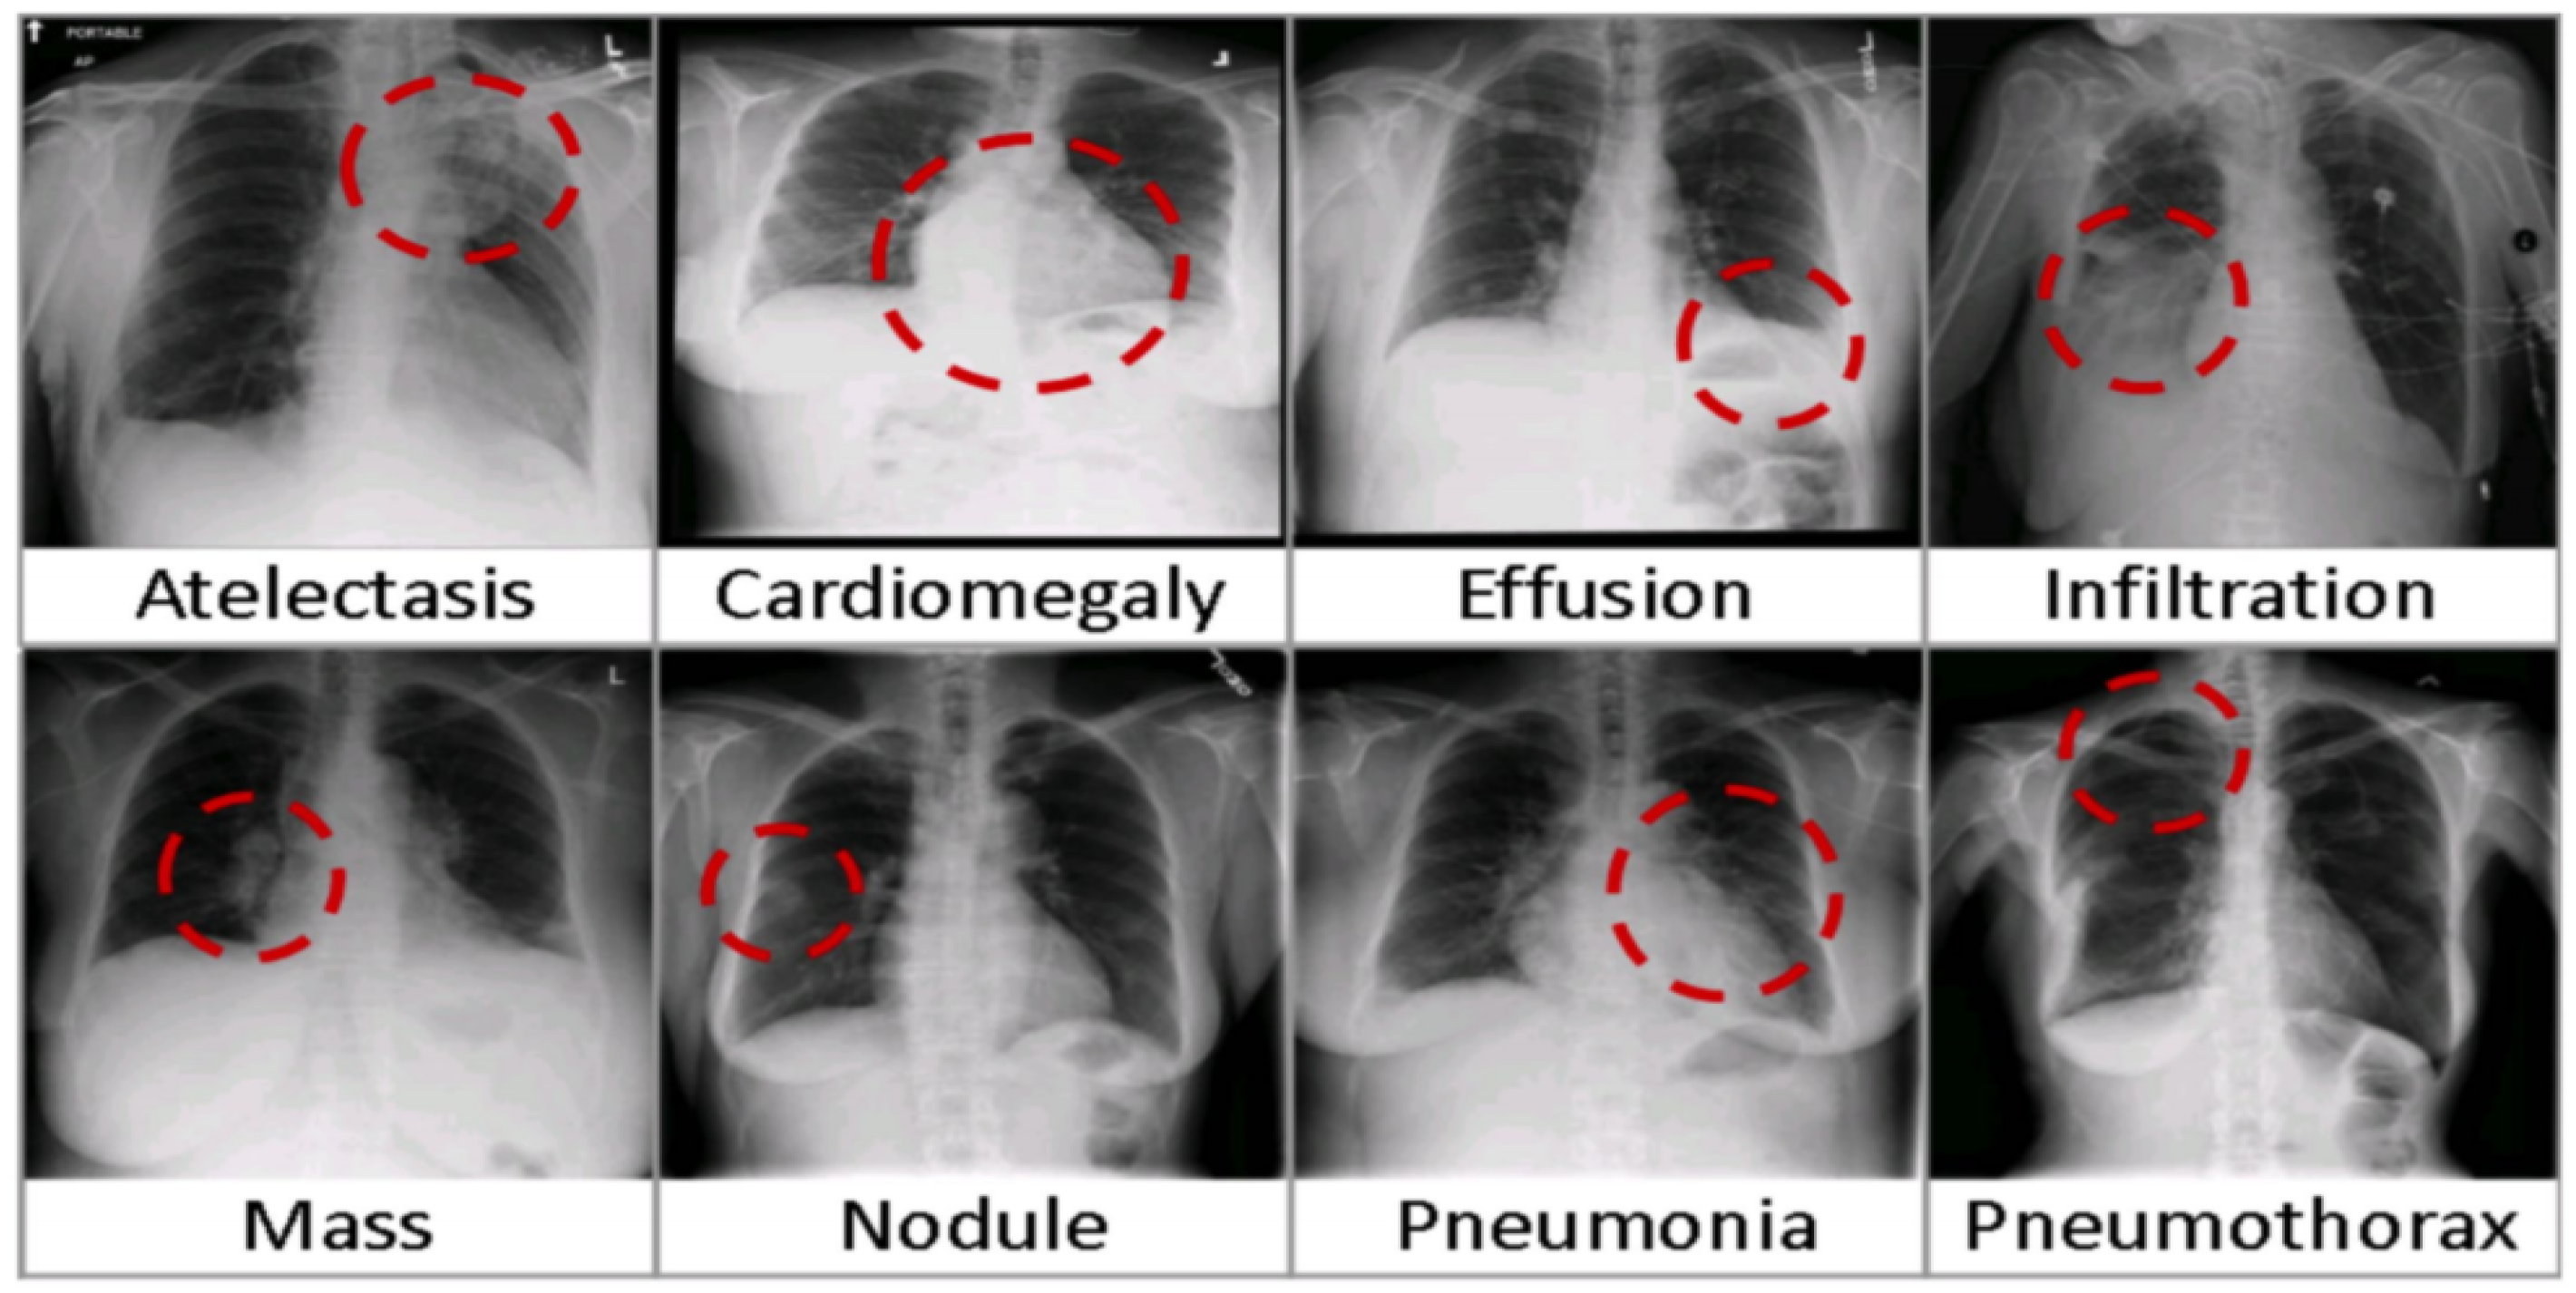

5. X-ray-14 Images Diagnosis

The Chest X-ray14 dataset encompasses a comprehensive collection of 112,120 frontal chest X-ray images sourced from 30,805 patients. This extensive compilation was meticulously assembled leveraging radiological summaries archived within hospital-based image storage and communication frameworks, subsequently refined through advanced natural language processing techniques. Each image within the dataset may exhibit signs of one or several common pulmonary conditions, with images labeled as “Normal” indicating a complete absence of detectable thoracic abnormalities (refer to Figure 9 for an illustration). The dataset is accessible for research and application at the following URL: https://nihcc.app.box.com/v/ChestXray-NIHCC (accessed on 2 February 2024).

Figure 9.

Frequent pulmonary conditions identified through chest X-ray imaging [51].

The comparative evaluation of various CNN design methodologies reveals intriguing insights into the performance of different optimization approaches. The obtained area under the receiver operating characteristic (AUROC) scores offer a gauge of each method’s effectiveness. The AUROC scores for manual optimization methods demonstrate a range from 78% to 84%. Yao et al.’s [30] manual approach yielded a respectable test AUROC of 79.79%, while Wang et al. achieved a competitive 73.81%. Meanwhile, the CheXNet method, also employing manual optimization, excelled with a test AUROC of 84.41.

In contrast, Google AutoML, a non-manual approach utilizing reinforcement learning (RL) for optimization, exhibited a relatively lower test AUROC of 79.72%. However, as the narrative unfolds, the trajectory of AUROC values takes an upward turn. Notably, LEAF, employing evolutionary algorithms (EA) for optimization, achieved a test AUROC of 84.29%, marking a notable improvement. This trend continued with NSGANet-X, another EA-based optimization approach, demonstrating impressive results with a test AUROC of 84.61%.

However, the pinnacle of achievement in this comparative landscape is exemplified by our method, denoted in the table. Operating under the framework of evolutionary algorithms (EA) for optimization, our approach delivered an outstanding test AUROC of 87.74%. This remarkable performance sets a new standard, surpassing the capabilities of previously explored methodologies and reaffirming the prowess of our approach in the realm of AUROC results on the ChestX-ray14 dataset. These results underscore the exceptional potential of our method in the pursuit of highly effective CNN architectures.